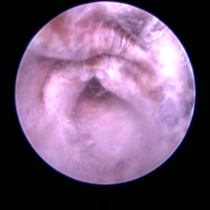

耳ダニ感染後の鼓膜喪失と中耳炎

長く耳ダニに気付かず治療が遅れた猫です。すでに鼓膜を失っており、中耳をきれいに洗浄すると赤い肉芽が確認できました。この肉芽を除去し点耳薬で治療すると改善。鼓膜が全く残っていないため鼓膜の再生は期待できませんが、痛みや痒みもなく元気に過ごしています。